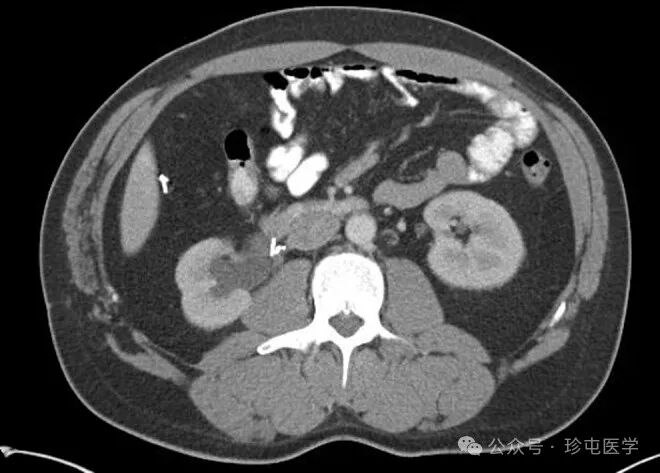

70F 有复发性 L UPJo 病史,s/p 之前接受过机器人 L 肾盂成形术,然后进行肾盂切开术 x2

腹部 CT 无造影显示手术夹靠近输尿管肾盂连接处 (UPJ)。从此图像很难判断手术夹是否正在侵蚀输尿管。